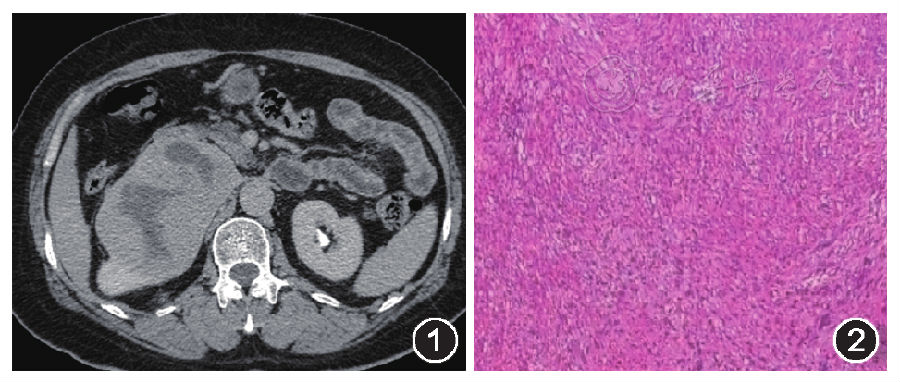

肾神经鞘瘤一例报告

900x382 - 90KB - JPEG